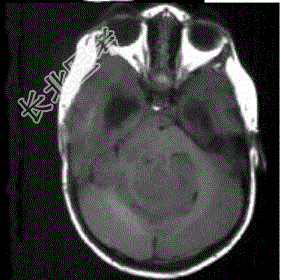

- 单项选择题成年男性患者,头痛、头晕、恶心, 病程2年余,结合影像图像选择最可能的诊断

A、星形细胞瘤

B、畸胎瘤

C、脑膜瘤

D、室管膜瘤

E、胶质瘤